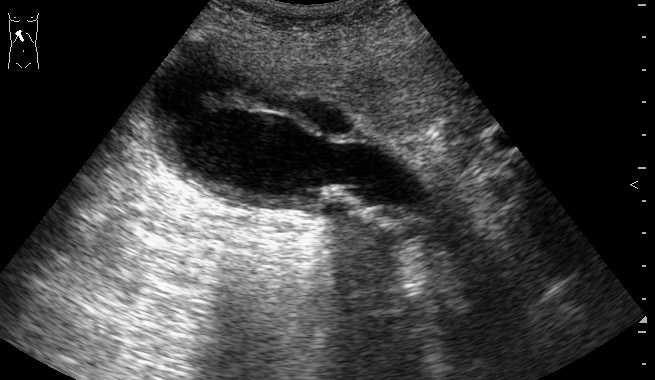

Пожилой мужчина, обратился в приемный покой БСМП с жалобами на периодические тупые боли в эпигастрии и правом подреберье. Год назад были сильные боли в правом подреберье, лечился самостоятельно дома.

Я бы поставил на основании выше показанного и изложенного - Холецистолитиаз, обострение. :)

слизистая в просвете желчного пузыря, что говорит о некрозе его стенки ... острый калькулезный холецистит, с перфорацией.. :ugeek:

при поперечном сканировании на втором ролике, скопление свободной жидкости в паренхиме печени :twisted:

Острый калькулезный гангренозный холецистит.

Особенность этого случая в том, что создается впечатление о перфорации стенки пузыря в области дна и наличии скопления желчи в области ложа пузыря.

В действительности перфорации стенки пузыря не было.